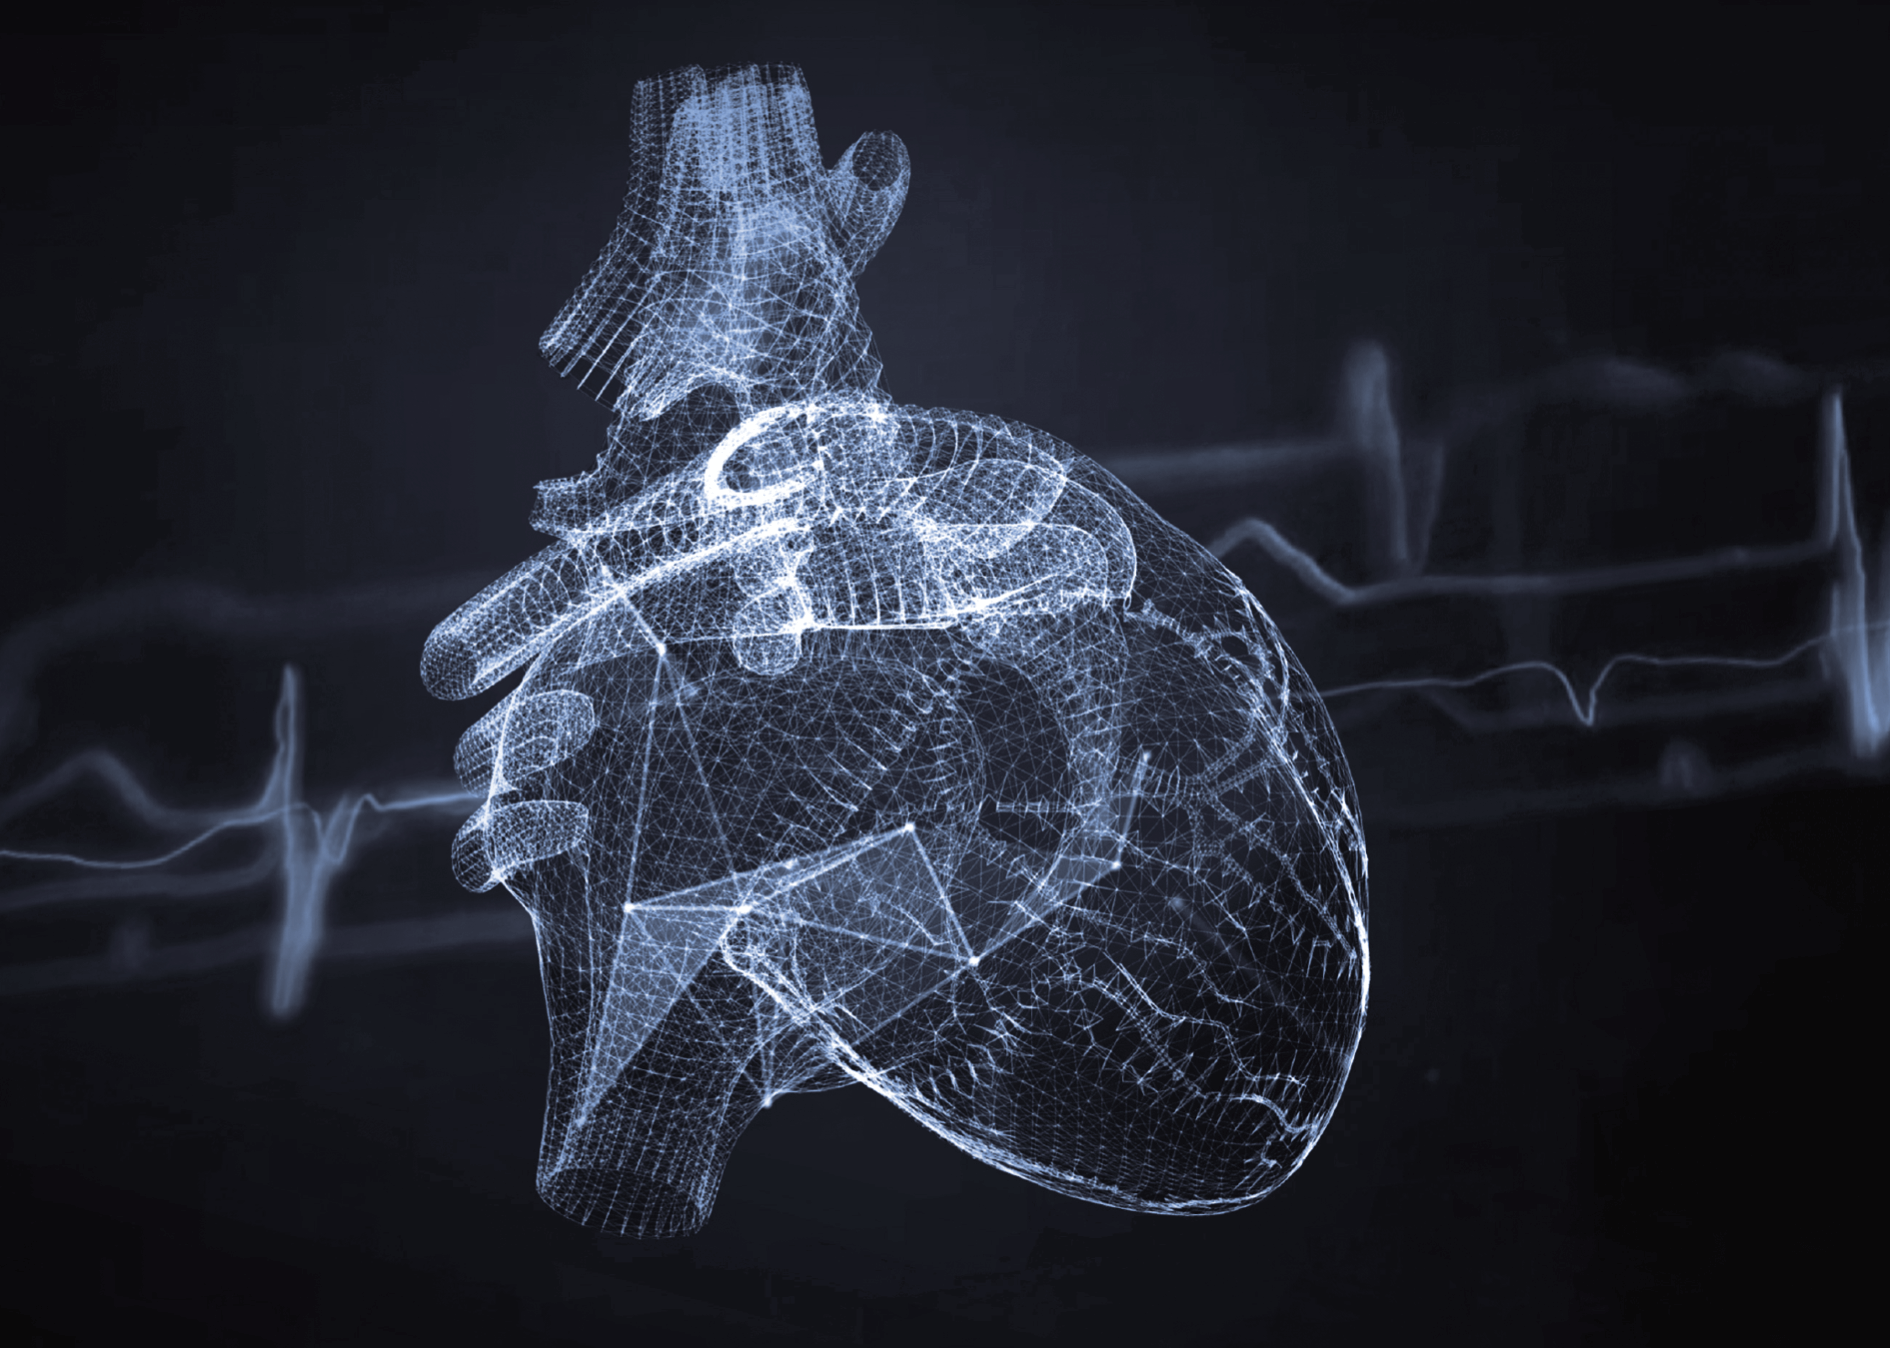

冠脉瞬时冻结技术

高级应用软件平台

高度智能,精准分析